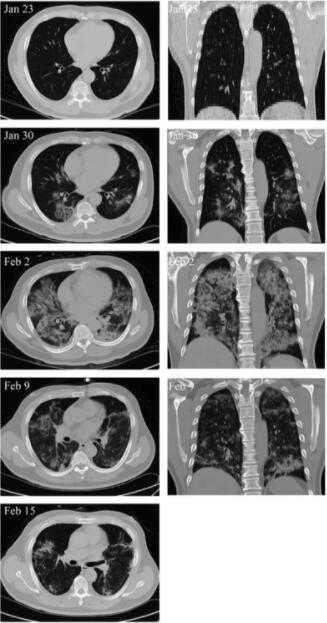

另外,MSC移植能顯著加快治療進程。移植后4天,新冠肺炎危重癥患者呼吸頻率降至正常范圍、發(fā)燒和呼吸急促等癥狀消失。移植后9天,胸部CT成像顯示毛玻璃樣混濁和肺炎浸潤已大大減少。

危重患者肺部影像學顯示癥狀改善